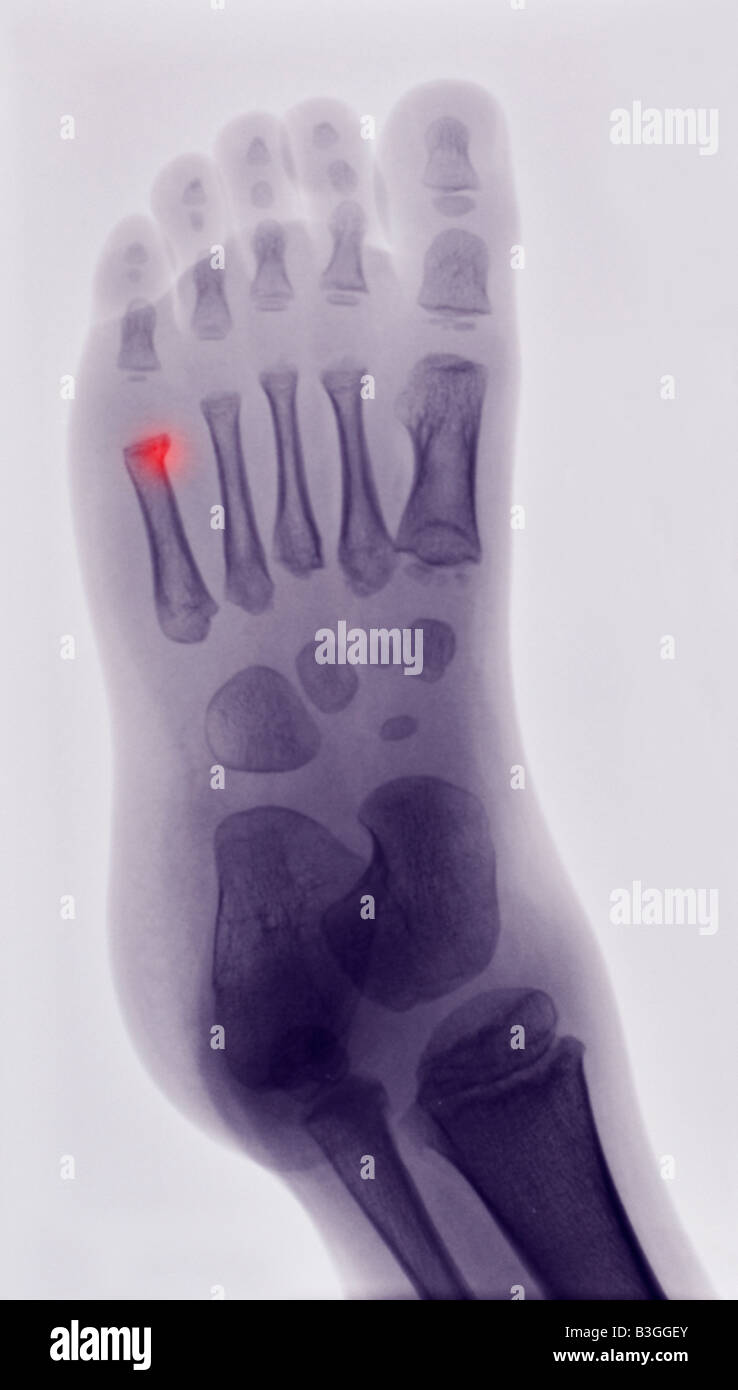

x ray of the foot of a boy showing a buckle fracture of the 5th What Is A Buckle Fracture In Your Foot Toe and forefoot fractures can result from a direct blow to your foot—such as dropping a heavy object on your toes. One of the most common bone injuries in children is a buckle fracture. The bone “buckles” on one side, but does not break all the way. They can also result from the overuse and repetitive stress that comes. It. What Is A Buckle Fracture In Your Foot.